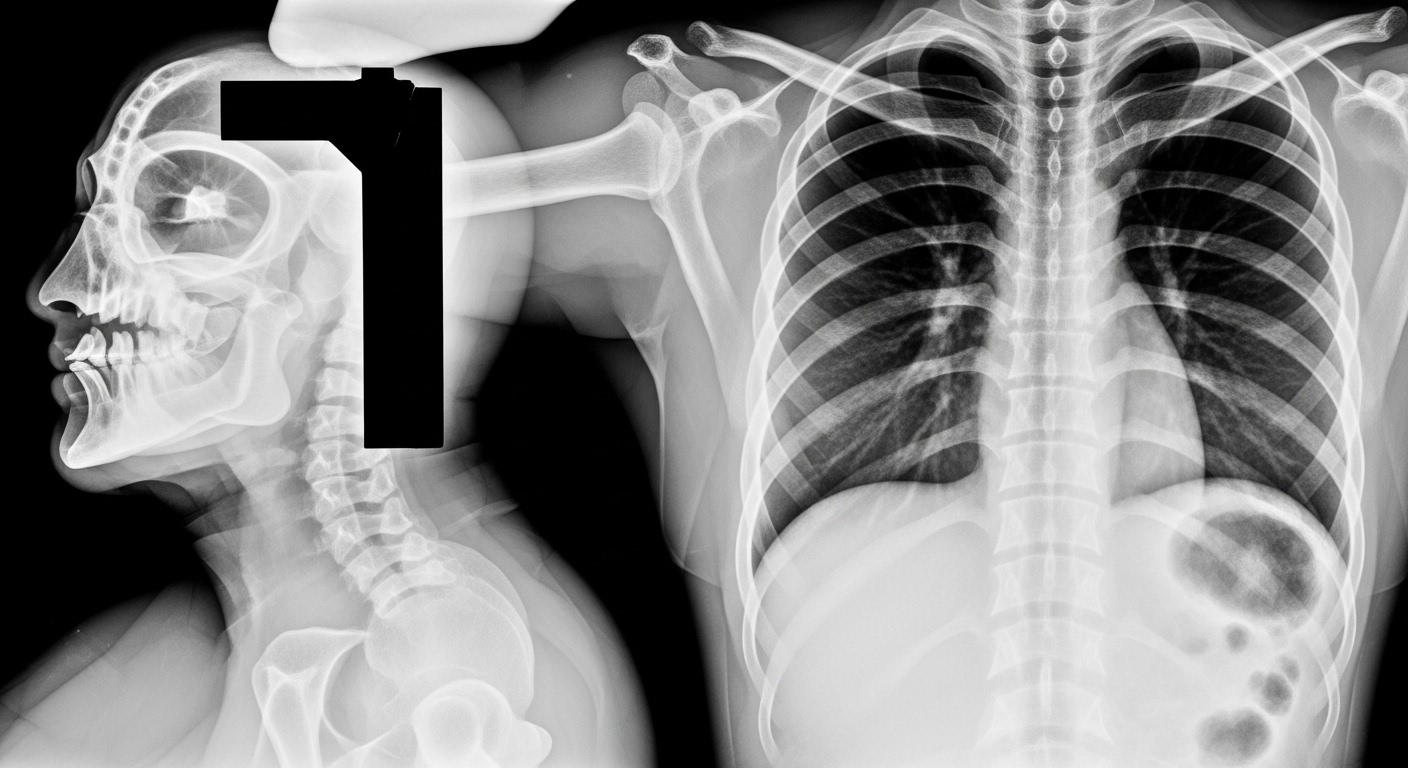

Os raios-X são uma forma de radiação que é absorvida de maneira diferente pelos tecidos humanos. Tecidos mais densos, como os ossos, absorvem mais radiação e, consequentemente, aparecem mais brancos nas imagens. Em contrapartida, tecidos menos densos, como os pulmões e músculos, absorvem menos raios-X e aparecem em tons mais escuros.

O resultado final são imagens em cortes transversais que podem ser visualizadas individualmente. Além disso, os softwares modernos permitem que essas “fatias” sejam empilhadas digitalmente para criar modelos tridimensionais (3D). Dessa forma, o médico consegue observar órgãos e vasos sanguíneos de qualquer ângulo, facilitando a identificação de anomalias mínimas.